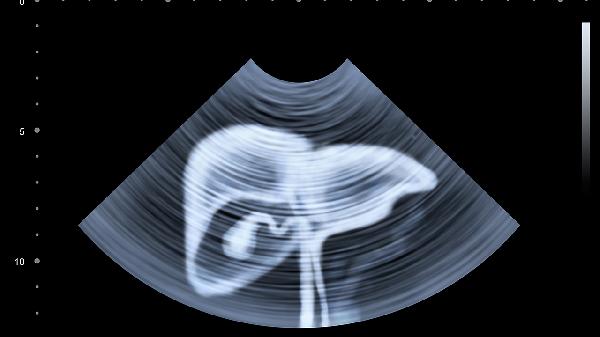

肝脏疾病进展往往悄无声息,当出现上述症状时,建议立即就医检查。常规体检中的肝功能检查和腹部超声是筛查肝病的重要手段。对于有乙肝、丙肝、脂肪肝病史或长期饮酒的人群,更应提高警惕,定期进行专项检查。早期发现、早期干预是提高肝癌治疗几率的关键。